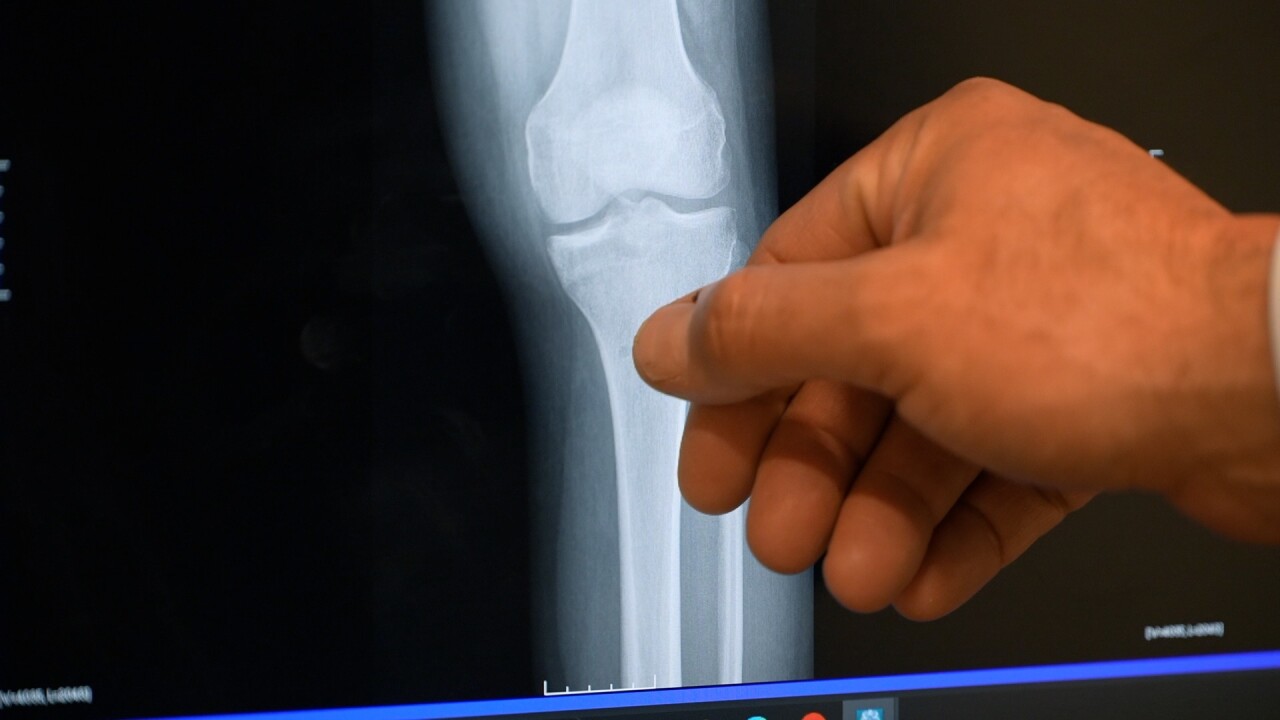

ACL X RAY

Conklin had torn his ACL. He thought he’d be sidelined from his favorite sport for a long time—until he met Dr. Brandon Beamer.

“The historical treatment for ACL injuries is to reconstruct the ACL. Basically, you remove the torn ACL and then put something else in that will turn into an ACL again someday,” Beamer explained.

That’s why Beamer was eager to try a new approach—the BEAR implant, which stands for Bridge Enhanced ACL Restoration.

“We’re actually sewing the ACL back together, but then providing it with an environment with this BEAR implant,” he said.

The BEAR implant, which resembles a marshmallow, insulates the injury and allows the ACL to repair itself. Beamer first learned the procedure at Harvard and became the first doctor to perform it in Montana, with Conklin as his first patient.